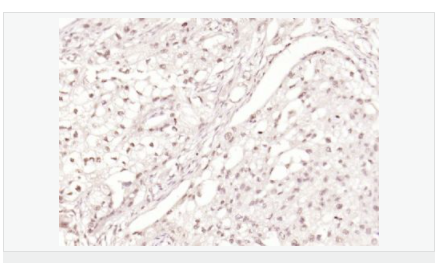

| 产品应用 | WB=1:500-2000 ELISA=1:5000-10000 IHC-P=1:100-500 IHC-F=1:100-500 Flow-Cyt=1μg/Test ICC=1:100 IF=1:100-500 (石蜡切片需做抗原修复) not yet tested in other applications. optimal dilutions/concentrations should be determined by the end user. |